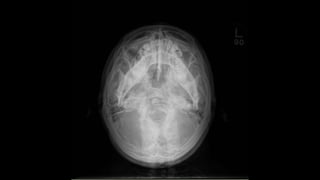

Submentovertical view

 It is an angled inferosuperior radiograph of the base of skull.

z Submentovertical view  Itis an angled inferosuperior radiograph of the base of skull.  Any cervical spine pathology should be ruled out before performing this view.  If erect, patient sits and leans back head facing away from the receptor.  If supine use pillow to elevate and tilt head backwards.  The head is tilted until IOML is parallel to the receptor and the vertex is in contact with the receptor. Beam centred 4cm inferior to mental point. • collimation • anterior to include mandibular mentum • posterior to include occipital bone • lateral to include the skin margin

Angulated fracture ofthe left zygomatic arch.